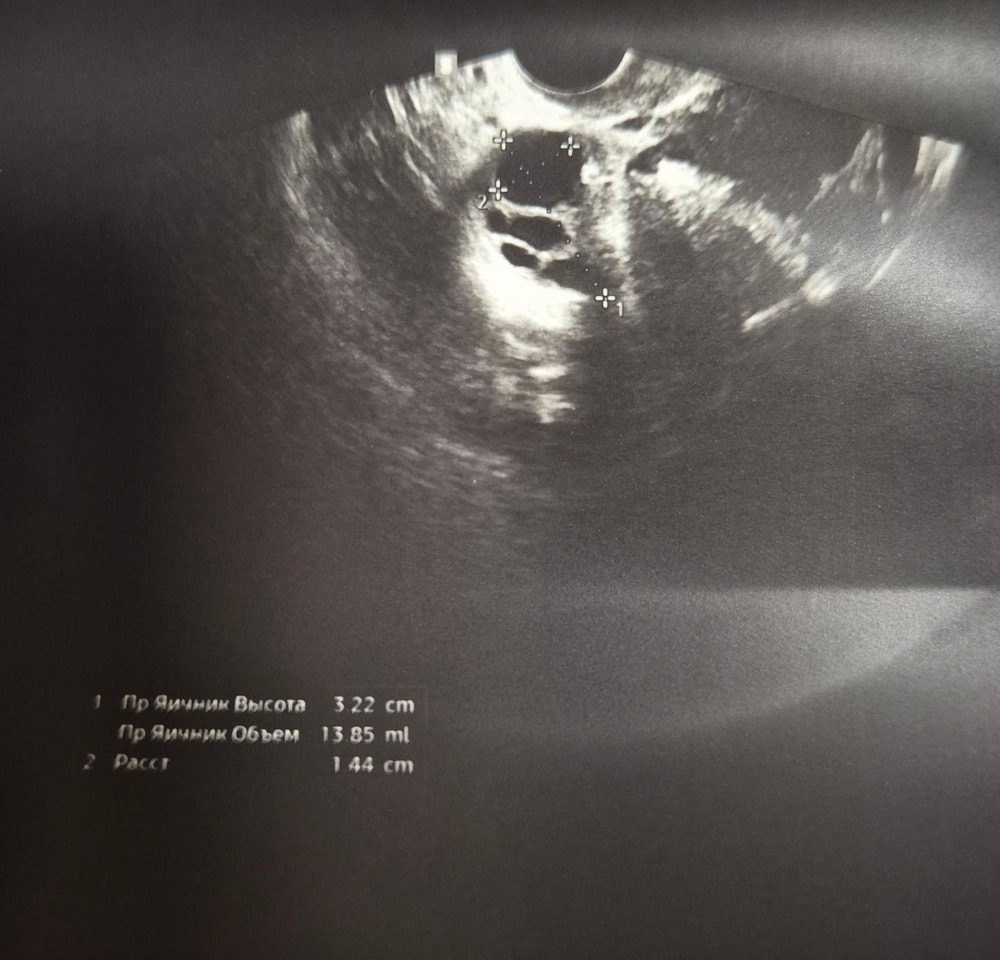

VILLI в Зачатие 6 месяцев Узи на 22 дц УЗИ Девочки, кто разбирается в узи. Помогите, что это ? Врач сказала все хорошо, кист никаких нет. Дома уже открыла снимки а тут такое 🙈 Посмотрите еще 20 записей на эту тему Отменить Ответить УЗИ 5 недель Насколько все плохо? Чаты Беременных Выберите чат: Январята-2026 Февралята-2026 Мартята-2026 Апрелята-2026 Майчата-2026 Июнята-2026 Июлята-2026 Августята-2026